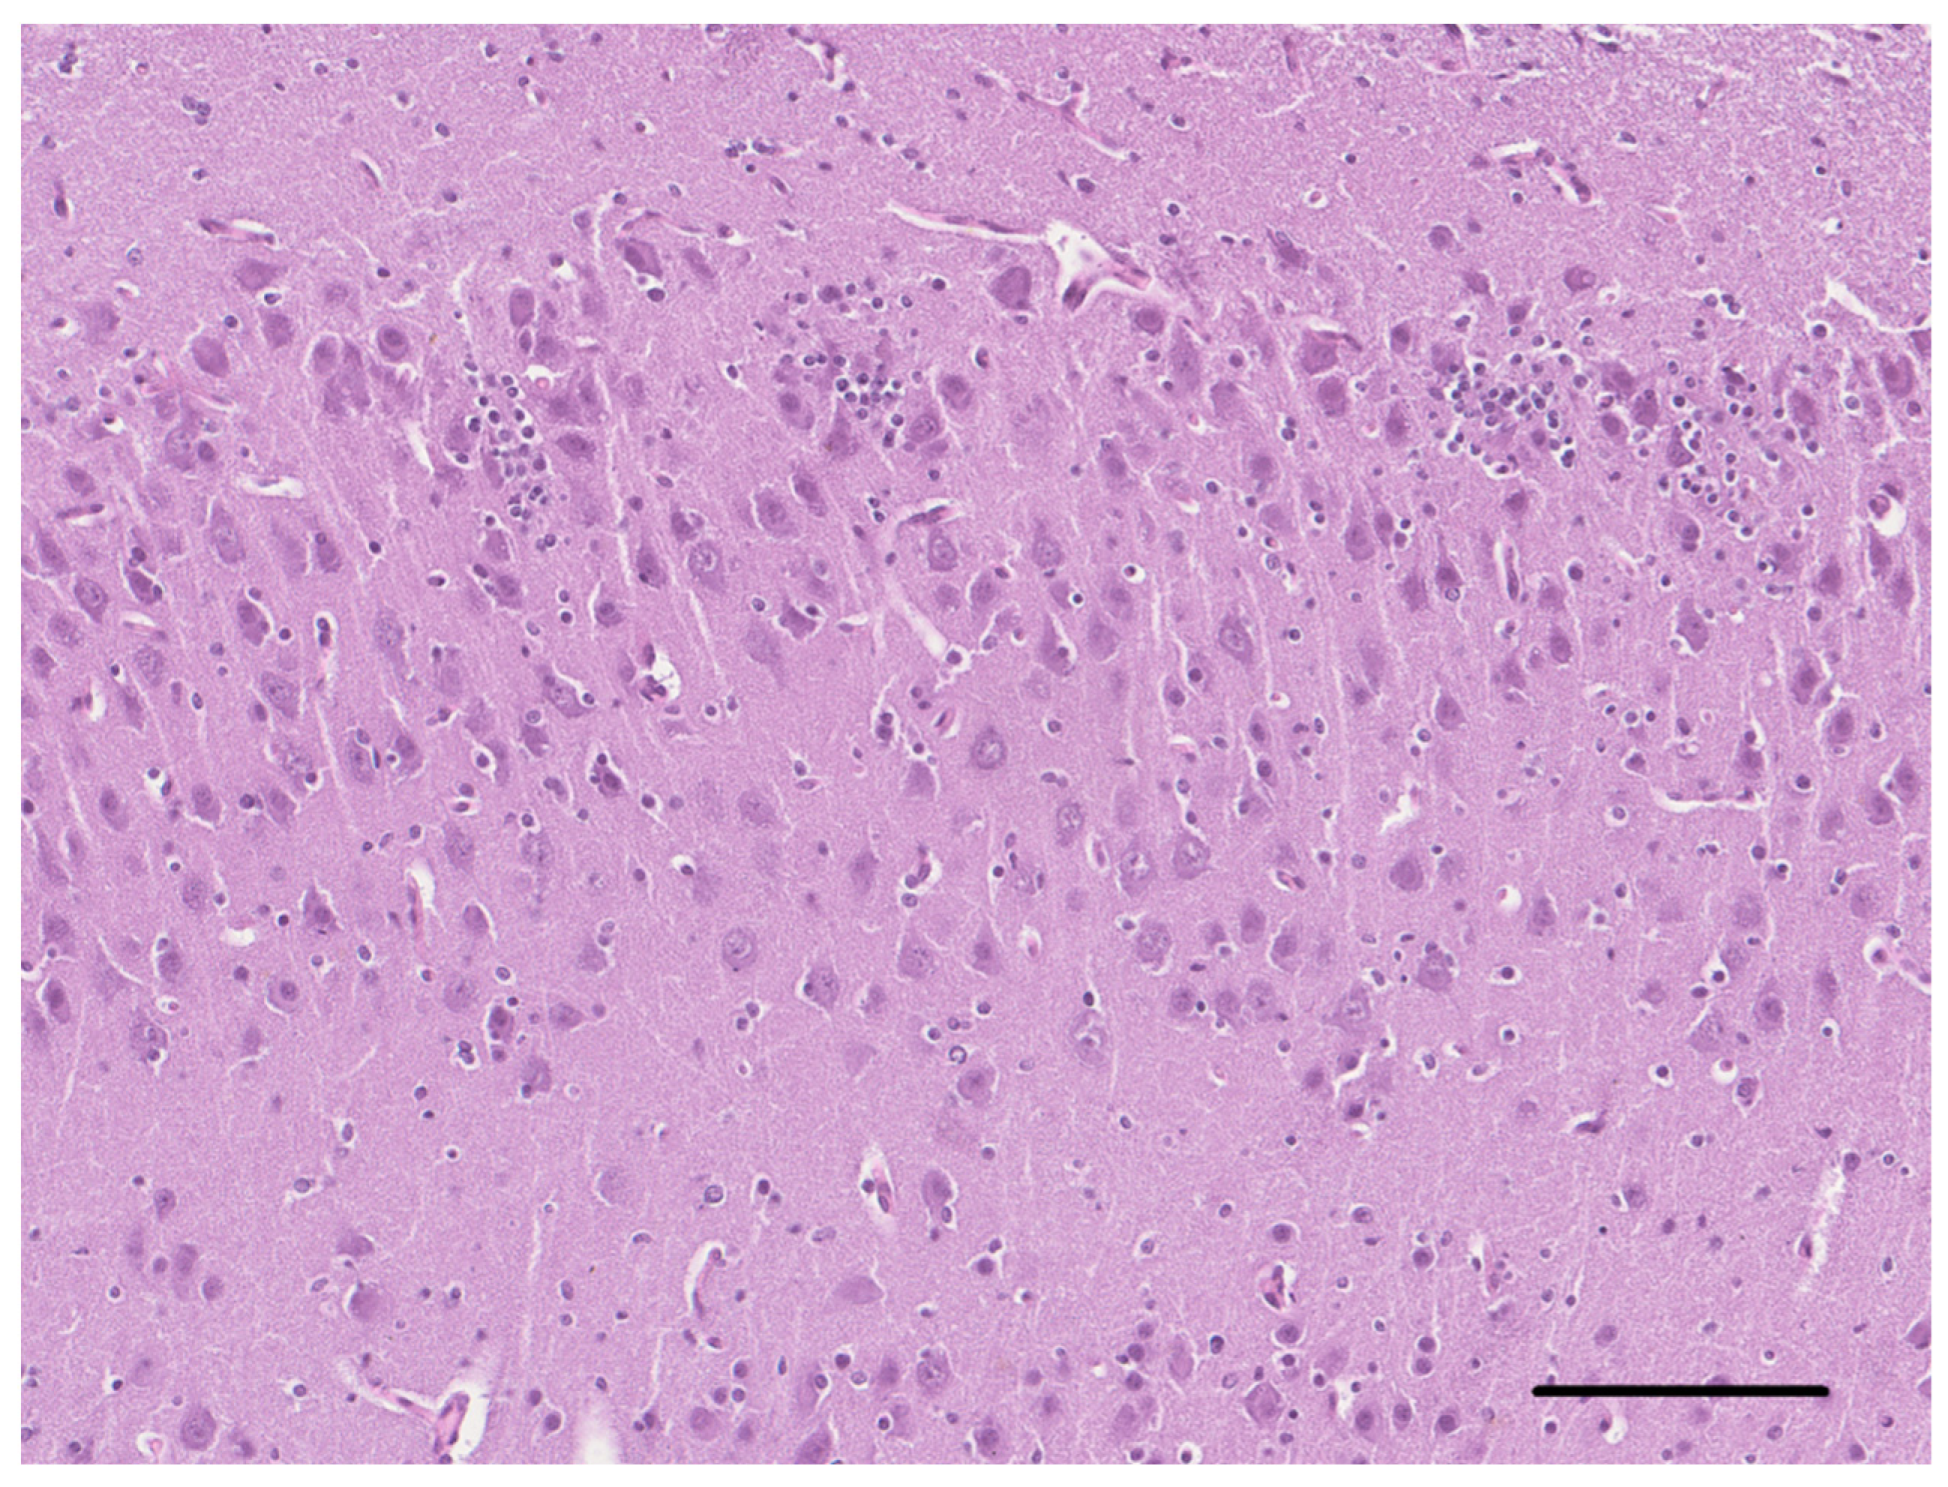

2. Case Description